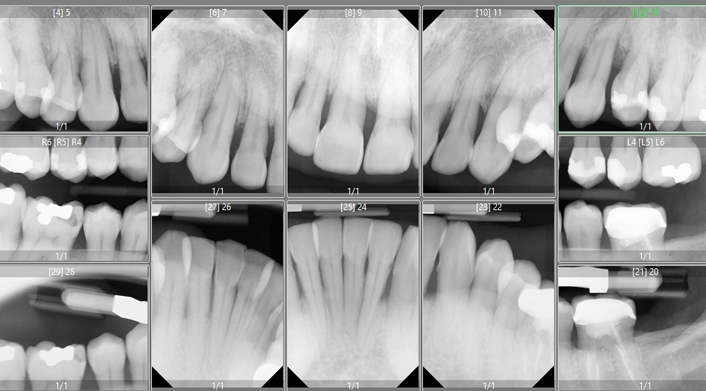

A part of your exam

is taking multiple diagnostic x-rays in addition to Digital intraoral 3D scan. The initial conversation is then followed by comprehensive exam which includes simple oral cancer screening, periodontal evaluation and probing, checking for signs of clenching or grinding as well as assessing your TMJ functions.